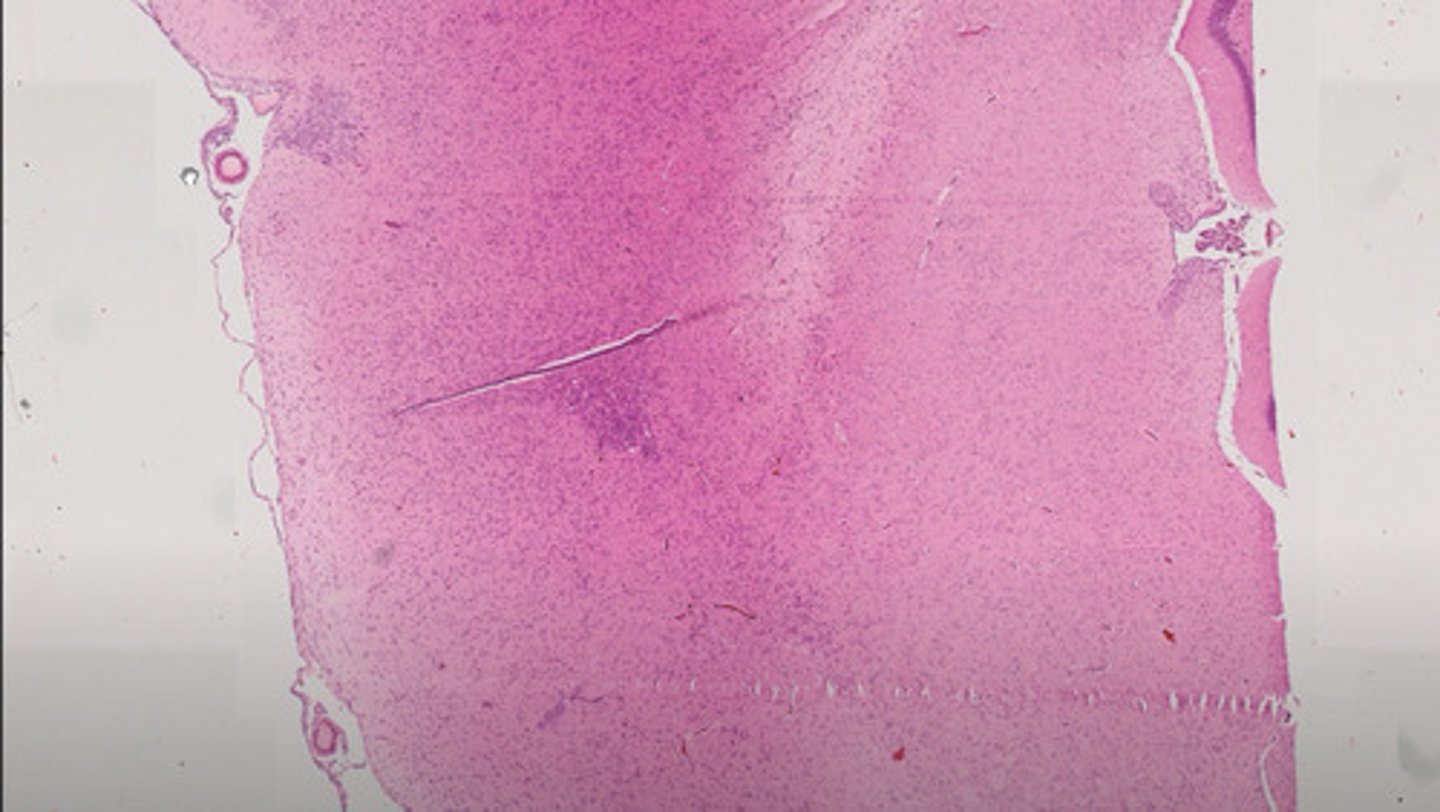

Śledziona (H+E)